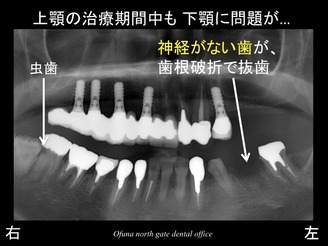

以下が初診時のレントゲンになります。

患者様は、まだ40歳の方です。

下顎は、ほとんどの歯は残っていますが、

上顎では残っている歯は、3歯だけです。

その他の歯はありません。

30歳代の10年間に 上顎の ほとんどを抜歯したそうです。

差し歯が取れた上顎前歯部の歯は、歯根破折 していました。

歯根破折 は、神経がない歯で起こります。

神経のない歯は、非常に脆く、通常の噛む力でも折れたりすることが高頻度で起こります。

折れた場所にもよりますが、歯根破折 した場合には抜歯となります。

一つは、神経のない歯が非常に多いというこです。

以下の赤丸(●印)が神経がない歯です。

ほとんどの歯が神経がありません。

40歳でこの状態ですから、このまま50歳、60歳…と考えると非常に心配な方です。

また、虫歯のリスクも高いことが分かりました。

しかし、上記のレントゲンからも分かるように 下顎の左側の奥から2番目の歯がありません。

これは、神経のない歯が歯根破折 を起こしたため、抜歯したのです。